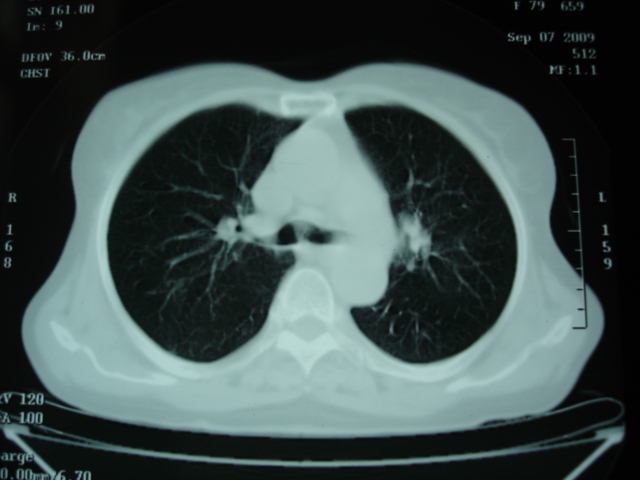

以下是引用卜一在2009-9-7 19:51:00的发言:[br][br] 1 左侧胸内甲状腺占位-多考虑甲状腺腺瘤! 2、左肺门占位-建议增强扫描以便明确性质。 3 慢支并感染! [br]

以下是引用shibing在2009-9-7 20:40:00的发言:[br]左侧胸内甲状腺占位-多考虑甲状腺腺瘤! 2、左肺门占位-建议增强扫描以便明确性质。 3 慢支并感染! [br]